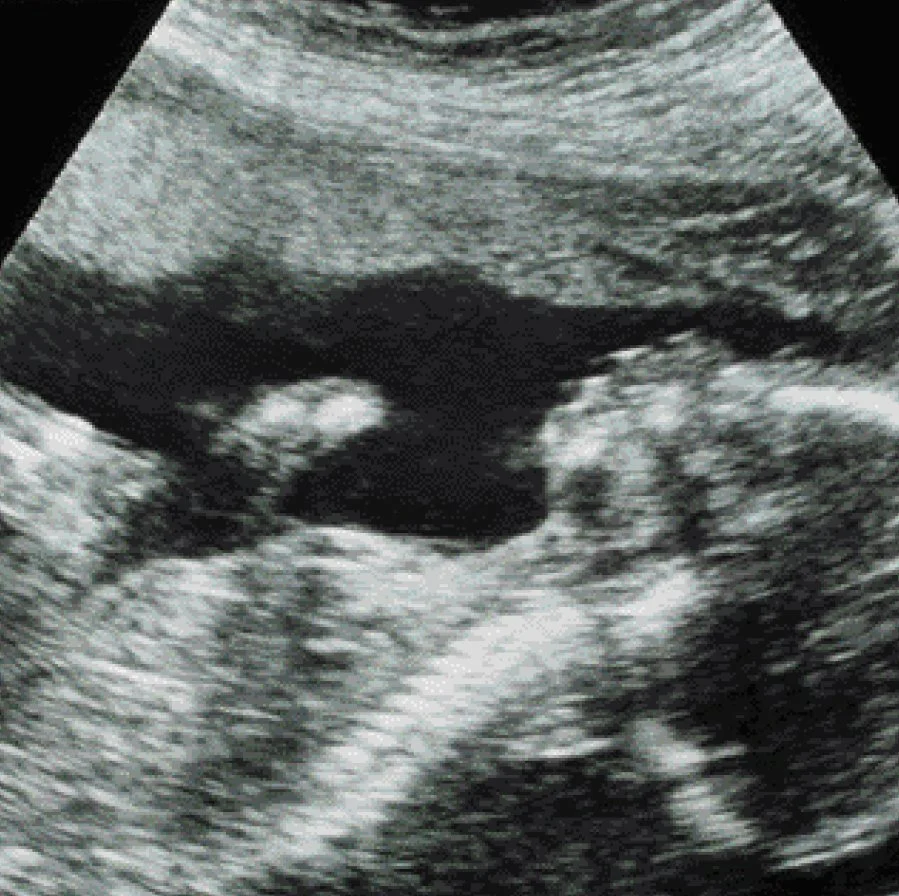

의료 초음파 영상은 소노그래프(sonograph)라 불리는 검사 장치를 이용해 신체조직에 저에너지의 고주파 음파를 적용한다. 위 그림의 경우, 태아 내부조직의 특성을 반사하는 음파를 기반으로 이미지가 재구성된 것이다.